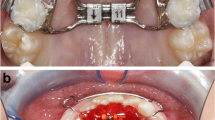

Dentoalveolar measurements of second premolars on coronal view. A, D a, the transverse width of the second premolar, distance from buccal cusp to the MSP; b, bucco alveolar crest width; c, bucco midalveolar widths; B, E d, palatal alveolar crest width; e, palatal midalveolar widths; C, F θ, the inclination of the second premolar

Dentoalveolar analysis

Dentoalveolar measurements were made on the second premolar (Fig. 3) and first molar (Fig. 4) of both arches. The midalveolar widths of the maxilla and mandible were determined at 7 mm apical to the alveolar crest [14]. The inclination of the second premolar and the first molar was determined as the angle between the long axis of the tooth and the vertical reference line. For single-rooted molar and premolar, the long axis was defined as the line connecting the groove between the buccal and palatal cusps and the root apex. For multi-rooted molar and premolar, the long axis was defined as the line connecting the groove between the buccal and palatal cusps and the furcation of the roots.

Dentoalveolar measurements of first molars on coronal view. A, D a, the transverse width of the first molar, distance from mesiobuccal cusp to the MSP; b, bucco alveolar crest width; c, bucco midalveolar widths; B, E d, palatal alveolar crest width; e, palatal midalveolar widths; C, F θ, the inclination of the first molar